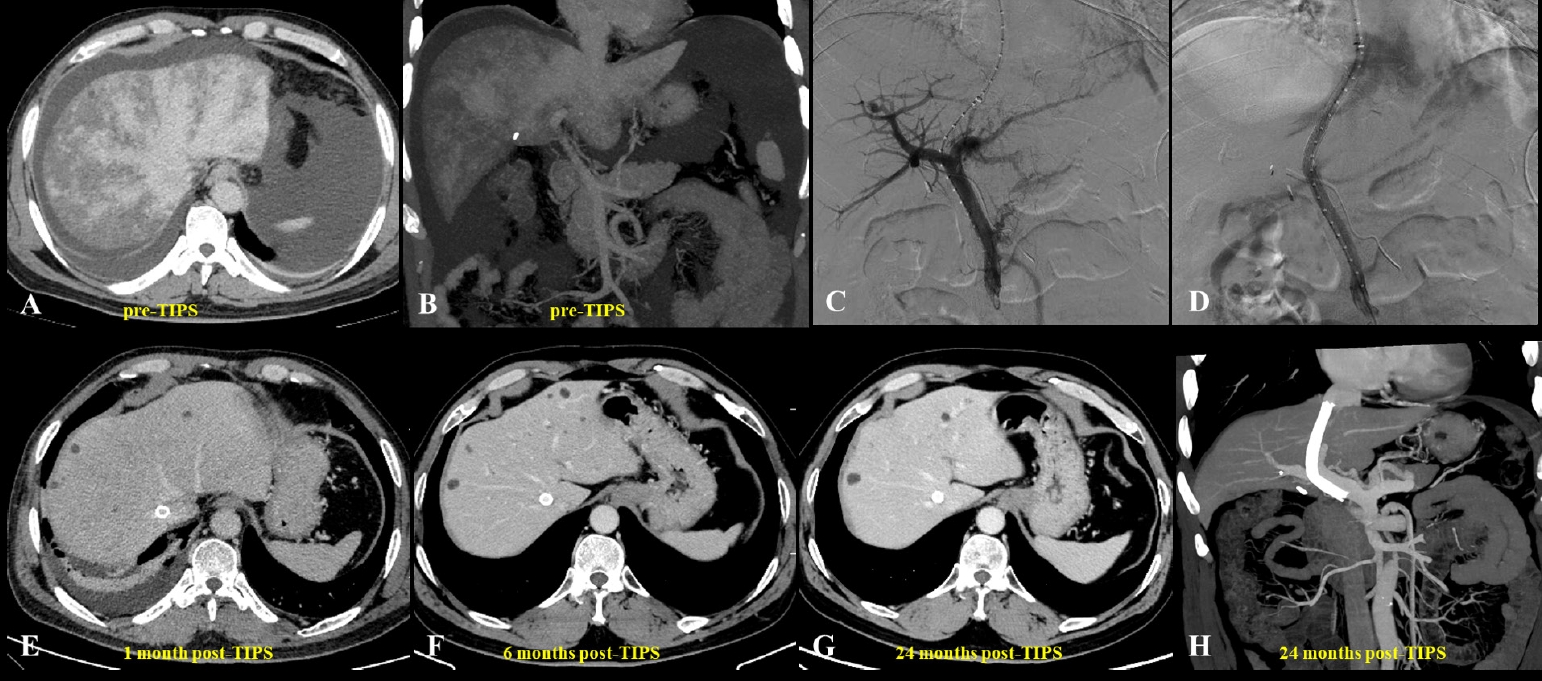

- Review Article Mar 23, 2026 Clinical challenges and transjugular intrahepatic portosystemic shunt strategies for pyrrolizidine alkaloid-induced hepatic sinusoidal obstruction syndrome: an Asian perspective Tan-Yang Zhou, Hong-Liang Wang, Zhi-Cheng Jin, et al. Korean J Interv Radiol 2026;31(1):24-35.